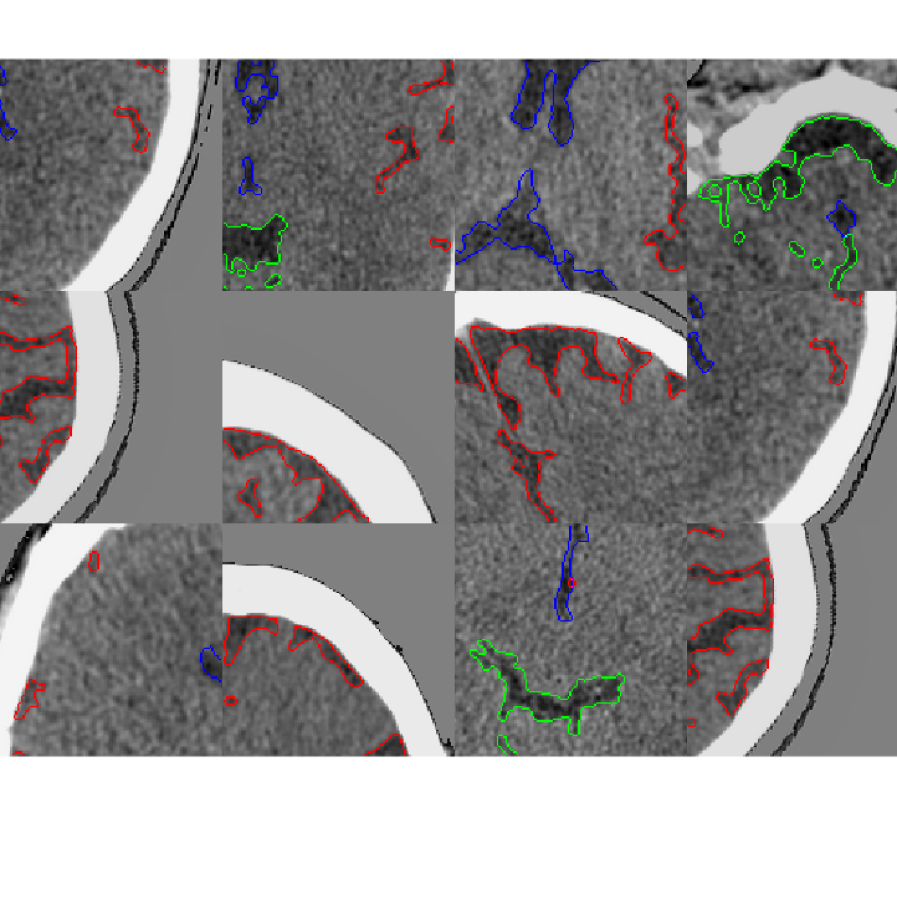

Refer to caption

(a) Real CT

(b) Synthetic CT

(c) Real MRI

(d) Synthetic MRI

Figure 1: Examples of real and GAN generated synthetic patches. Left CSF. Red: Cortical CSF. Green: Brain stem CSF. Blue: Ventricular CSF. Right: WMH.

Table 1 summarises the five sets of experiments which were carried out to answer the questions posed earlier. In each experiment, the segmentation network is treated as a black box and unchanged. This provides a fair platform upon which to observe the effects of GAN augmentation by ensuring that any changes in performance are as a result of the additional synthetic data, and not of changes in the network itself. GAN training took 36 hours, each UNet took 4 hours, each Res-UNet took 24 hours and each DeepMedic network took 24 hours on an Nvidia GTX 1080 Ti or similar GPU. All segmentation experiments on CT were repeated 8 times, while those on MR were repeated 14 times to compensate for a higher observed variance. Examples of real and synthetic patches generated for each dataset can be seen in Figure 1.